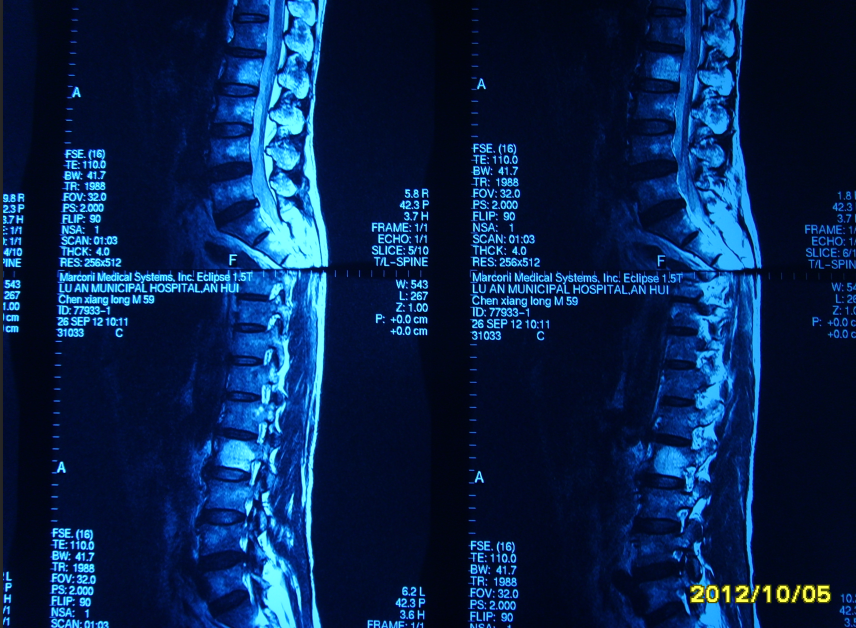

脊柱微创手术(PVP、PKP)已为常规手术,图PKP为脊柱多发血管瘤,图PVP为83岁高龄患者腰椎多发骨折。